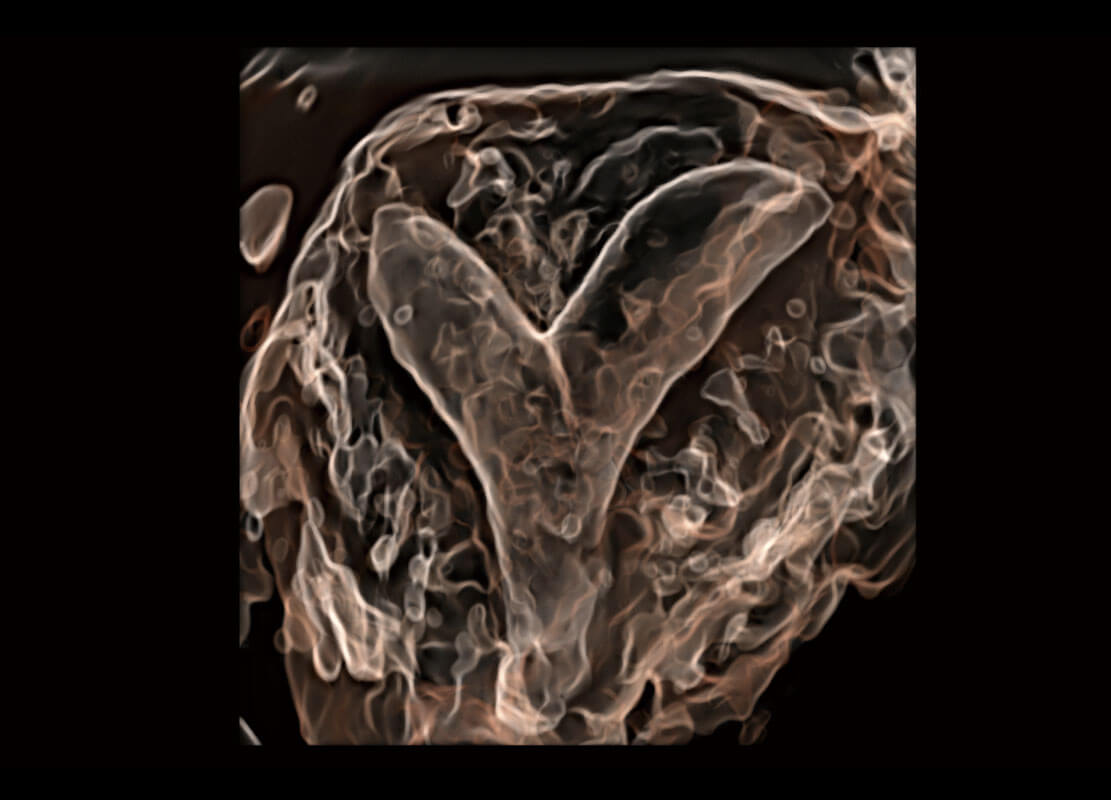

• 腔内三维-宫内节育器

• 腔内三维-光影成像

• 光影成像-孕囊

• 胎心容积成像